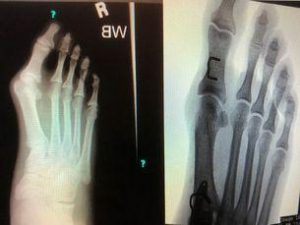

Bunions come in a variety of shapes and sizes, from mild to severe, which is determined by their clinical appearance, physical examination and radiographic measurements. Depending on the severity of the bunion, the appropriate non-surgical or surgical approach can be determined.

There is a wide array of procedures for correcting bunions. Each patient is treated on a case by case basis and the bunion procedures are chosen based on radiographic evaluation as well as a biomechanical examination and structure of the foot.

Typically the procedures involve creating a surgical “break” (osteotomy) in the misaligned metatarsal bone to realign only a portion of the bone. A variety of shaped cuts can be performed to treat varying sizes of bunions. These procedures are reserved for mild to moderate procedures.

Joint freezing(fusion) procedures realign the entire deviated bone at the root of the problem, where the deviation originates. The name of this procedure is called the Lapidus Bunionectomy. This procedure is reserved for a severe bunionectomy or for moderate bunions that have increased instability at the 1st tarsometatarsal joint.